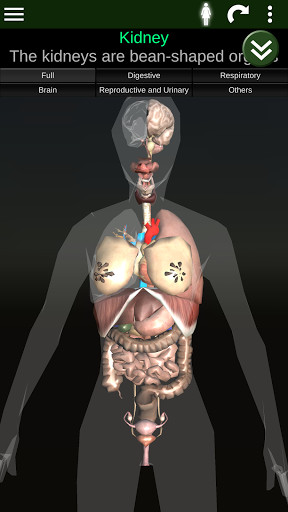

Toont een 3D-anatomisch model van de belangrijkste organen van het menselijk lichaam en een beschrijving van elk orgaan.

Wat zit er in de app?

* Spijsverteringsstelsel, inclusief de maag, dunne darm, dikke darm, en een animatie van dit systeem.

* Ademhalingssysteem, inclusief de luchtpijp, bronchiën, longen en een animatie van dit systeem.

* Voortplantingssysteem, dat de mannelijke en vrouwelijke voortplantingsorganen omvat.

* Hersenen, waaronder de hersenen, het cerebellum en de hersenstam vallen.

* Hart, dat de atria, ventrikels, aorta en een animatie van dit orgel omvat.

* Gemakkelijk te openen en te navigeren (zoom, 3D-rotatie).

Deze app is ontworpen als aanvulling op de studie van anatomie in verschillende onderwijs-, gezondheidszorg- en culturele omgevingen.

Praktische, nuttige en waardevolle anatomische informatie binnen handbereik.